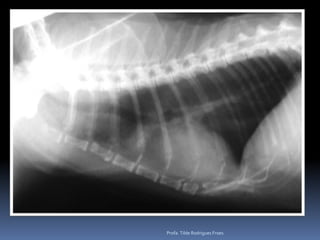

Animal: Dusty, felino, macho, 18 anos, SRDPesquisa de metastasesProfa. Tilde Rodrigues Froes

Animal: Dusty, felino,macho, 18 anos, SRDPesquisa de metastasesProfa. Tilde Rodrigues Froes